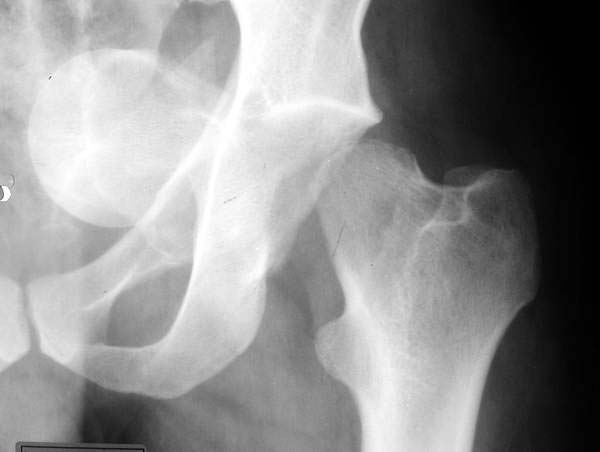

I agree with Mangal that this is certainly NOT the time to do a THR of any kind. Looking carefully at the CT And Xray images, the case is a central fracture-dislocation of the hip with a fracture neck of femur. the involvement of the antr and postr walls is not significant, mainly only the medial wall is involved. the femoral head is fully inruded into the pelvis. using traction is not going to bring the head out of this position. operating and removing this head fragment will be really difficult as there is no hold on this head to push & pull against.

I think IMHO that leaving it as it is and wait for the femoral head to resorb as will happen will be the best option so that there is no further trauma to this already seriously traumatised area and THR later will be a much easier option. if you think about it, the medial wall contributes very little to the stability of a THR anyway. the main areas of weight transmission are the superolat roof which seems intact here. there is an undisplaced fracture through the superior roof of the acetabulum which should heal fine with traction and bed rest, toe-touching WB thereafter.

I had one exactly like this. It was diagnosed acutely, and I took it to the OR in the middle of the night. The femoral head pulled out easily- fortunately no pelvic vessel injury. I fixed the femoral neck, and he went on to bipolar hip at one year. I would do it now before things heal in and scar down. I would recommend pelvic angio. If the vessels look displaced/involved, it can be approached thru retroperitoneal approach as is done with medial migrated hip components (references exist in JBJS for this) The thought of leaving the head where it lies is interesting. You could then just do a hip replacement as per your preference. Take the head out later if needed. The acetabulum is split superiorly, and needs to be plated. On the case I had, the acetabulum spread nicely with a lamina spreader, and this helped retrieve the head. A standard cup has plenty of bone to support it because the ant/post/superior columns are present. However, failure to plate the acetabular fracture will likely result in the cup not fitting snugly, even with screws thru the cup (which I would recommend). I personally would give him a metal-metal hip.

If, by some miracle, there is some soft tissue still attached to the neck, you could try to stuff it back through that hole. It probably won't fit. It looks like the tab opened up wide to let the head into the pelvis, then slammed back shut and trapped it. I bet that crack in the dome was displaced a lot when the injury occurred.